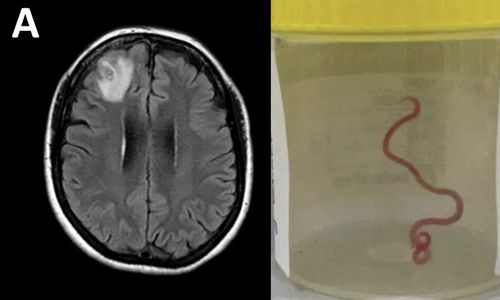

A parasitic roundworm typically found in snakes was pulled “alive and wriggling” from a woman’s brain in a stomach-churning medical first, Australian doctors said yesterday.

Baffled doctors performed an MRI scan on the 64-year-old Australian woman after she began suffering memory lapses, noticing an “atypical lesion” at the front of her brain.

It was an eight-centimetre (three-inch) roundworm, called Ophidascaris robertsi, which researchers said was a common parasite in kangaroos and carpet pythons -- but not humans.

She was re-admitted to a hospital three weeks later when her condition did not improve, and underwent various treatments until brain scans revealed a lesion and an open biopsy was performed in June 2022.

“We noted a stringlike structure within the lesion, which we removed; it was a live and motile helminth,” the findings said.